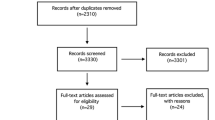

Plain radiographs and magnetic resonance imaging (MRI) are indispensable in the evaluation of patients with suspected PCL deficiency. Rosenberg posterior-anterior (PA) flexion weight-bearing radiographs of the affected knee are useful to assess for degenerative changes in the medial joint space. The Merchant’s view allows for inspection of the patellofemoral joint and detection of the degenerative changes typical of the chronically PCL-deficient knee. A precise understanding of the patient’s axial alignment and tibial slope informs the surgeon’s decision to perform an osteotomy and dictates the orientation and magnitude of the required correction. In the setting of a varus knee deformity, single cassette, full-length anterior-posterior (AP) standing radiographs of bilateral lower extremities is mandatory (Fig. 1). Moreover, the utility of single cassette, full-length AP supine radiographs of bilateral lower extremities has also been advocated in order to eliminate the added, dynamic varus deformity that may be a consequence of deficient lateral and posterolateral structures, which may complicate a precise understanding of the patient’s coronal plan alignment attributable solely to an underlying osseous anatomy [36, 59].

Single cassette, full-length anterior posterior standing radiograph of bilateral lower extremities is used to calculate required correction of varus malalignment in the coronal plane. Right knee: When OA changes are not present in the medial compartment, the correction should target for the mechanical axis to cross the tibial plateau at 50% of total tibial plateau width. The angle α represents the required correction. Left knee: If OA in the medial compartment is present, the correction should target for the mechanical axis to cross the tibial plateau at 62% of total tibial plateau width, from medial to lateral. The angle β represents the required correction